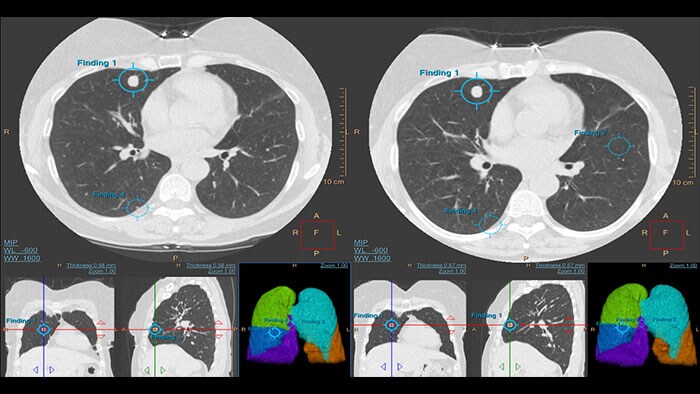

Pakiet zaawansowanych narzędzi do obrazowania pozwalający na segmentację, ocenę ilościową oraz monitorowanie wskazanych przez lekarza guzków płucnych. Aplikację można stosować zarówno w procedurach diagnostycznych, jak i w badaniach przesiewowych pod kątem raka płuc z wykorzystaniem niskodawkowego obrazowania CT (Low Dose CT Lung Cancer Screening)*.

– wykrywania guzków w płucach potencjalnie wymagających dalszych działań (nie tylko okrągłych obiektów lub obszarów ROI); – korelowania obrazów 2D, 3D i map płuc; – rejestrowania aktualnych lub poprzednio wykrytych guzków; – obliczania zmian, jakim uległy guzki.